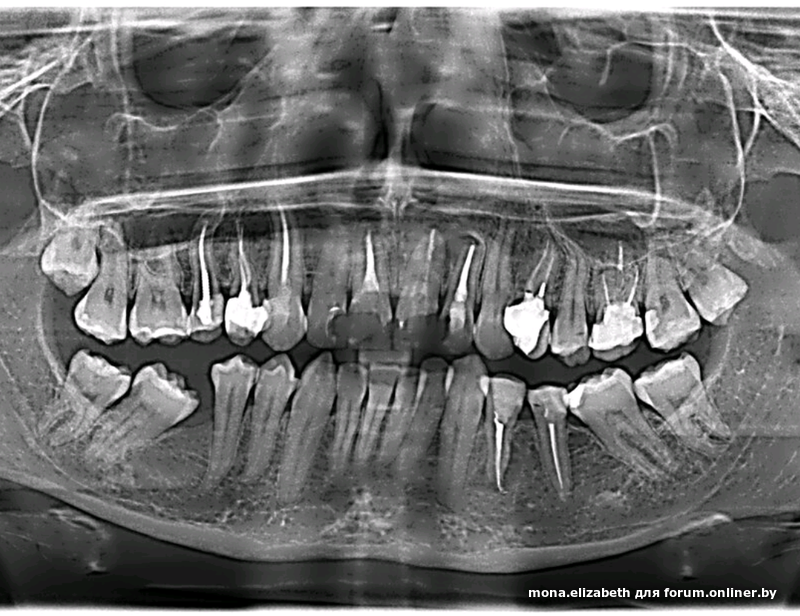

p/p/s/ Мне крайне любопытно, по каким причинам Гричанюк не может удалить 8ки в кресле.